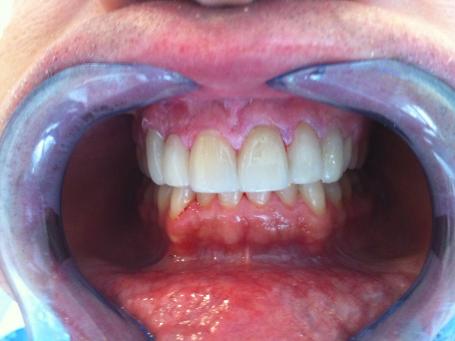

2°) Photo préopératoire droite.

Des facettes céramiques (céramiques pressées) sont réalisées dans le but de restaurer l’esthétique et un alignement idéal des dents.

Des préparations pelliculaires sont réalisés et des facettes provisoires sont laissés en place pendant 48h le temps de réaliser les facettes définitives.